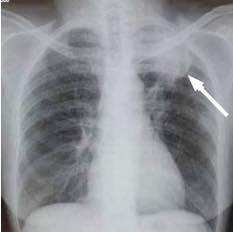

Very occasionally, if you're a smoker and have a bad cough, we would have to consider a Pancoast tumour in the apex of the lung. That too causes pain and tingling in the hand and arm as the tumour impinges on the nerves coursing their way from the lower neck, through the armpit on the way to the fingers.